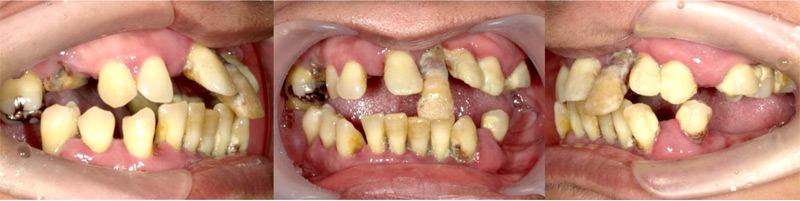

上顎、下顎のいずれか1列分の歯を、4本のインプラント体で固定する治療についての症例です。

施行名 : 審美歯科(虫歯などをインプラント体によって改善する施術)

副作用やリスク : 麻酔で腫れやむくみを生じる場合があります。

また、劣化や口内の手入れを怠ることにより脱落する場合があります。

施術の価格:8万〜90万(税抜き)

※個人差があり、効果を保障するものではありません